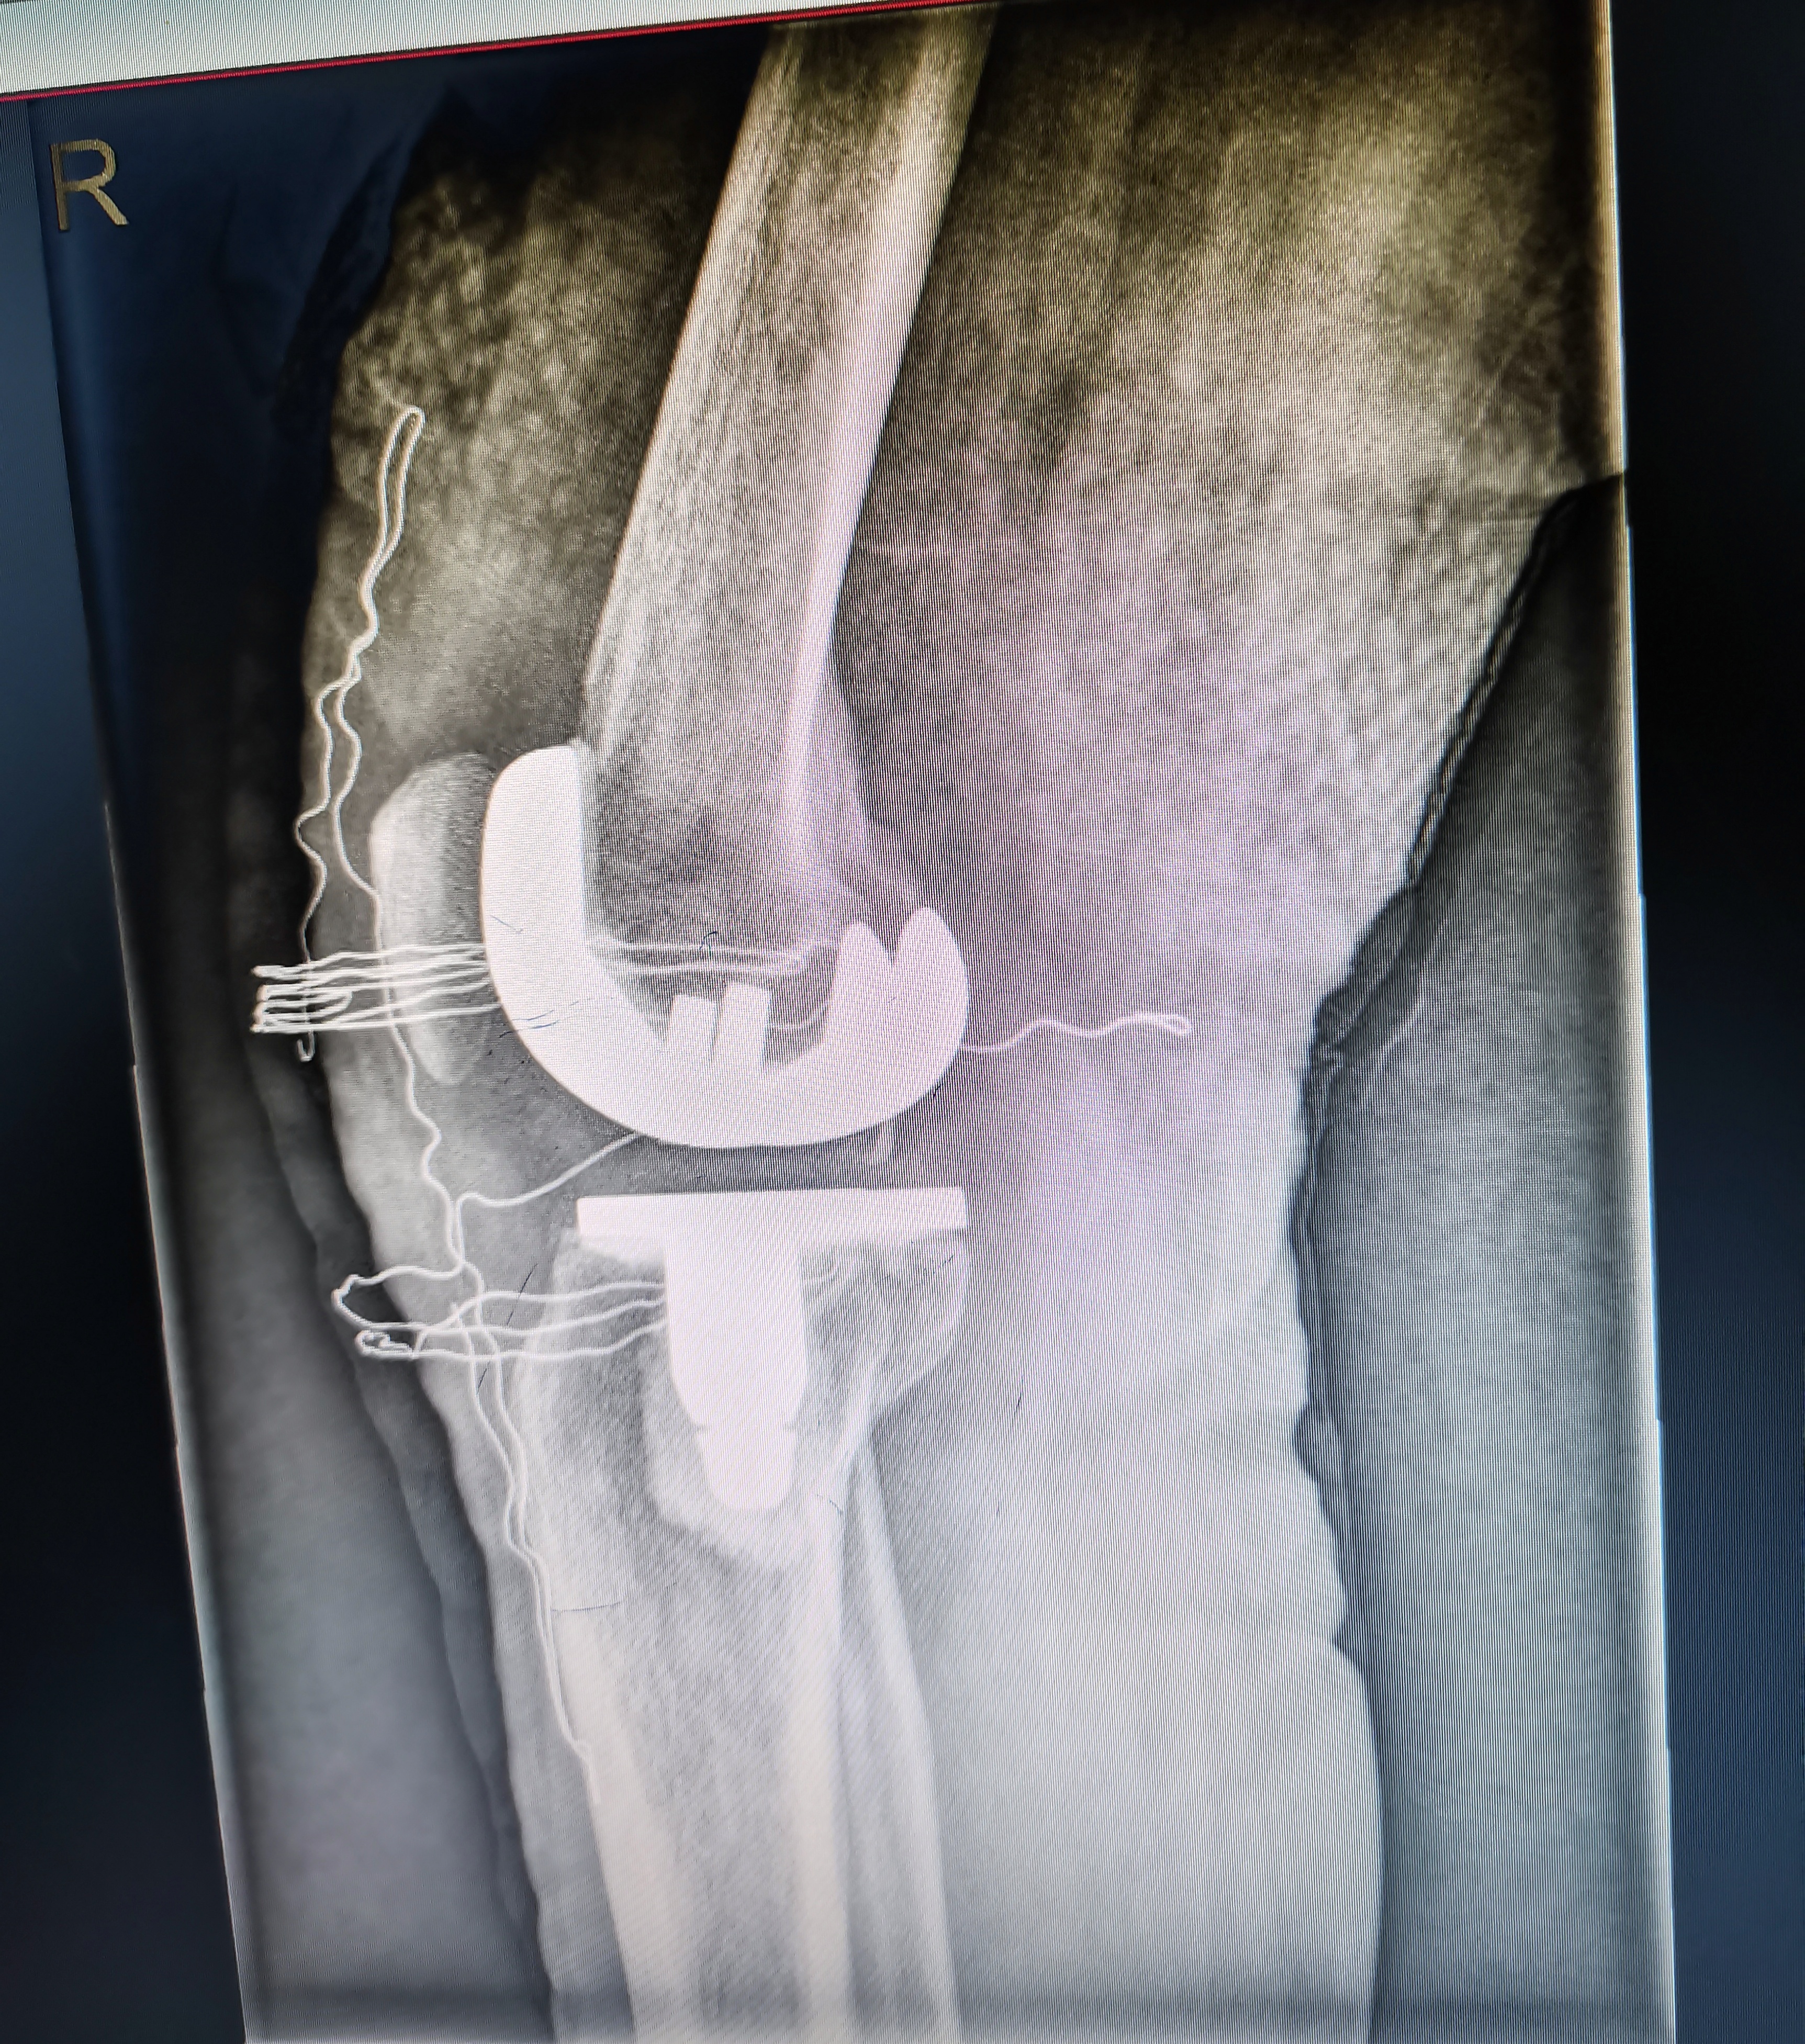

術后照片